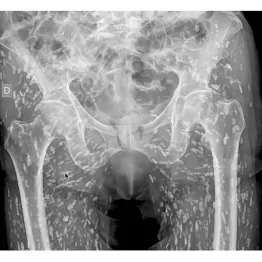

米フロリダ州の救急医がXに投稿…「最も異常なX線写真」が示す教訓

まさにホラーとしか言いようがない。米フロリダ州にある病院のERで救急医をしているサム・ガリ医師が「これまで見た中で最も異常なX線写真」として自身のXに投稿した写真に注目が集まっている。

写真はある患者(氏名非公開)の下半身を撮影したもので、骨のほかに無数の米粒のような白い影が映っている。これはなんとサナダムシの嚢胞が石灰化したものだという。

嚢胞というのはサナダムシの幼虫が入ったゼラチン状の袋のこと。

サナダムシは通常は宿主の腸内に寄生して栄養を吸収する。しかし、その嚢胞は宿主の体内のどこにでも移動することが可能だ。移動した嚢胞は時間がたつと石灰化し、生存能力を失う。基本的に無害だが、脳で石灰化すると「神経嚢虫症」と呼ばれる命に関わる病気になる恐れがあるという。

驚いたことに、この患者は自分の体内にサナダムシの嚢胞が無数にあることを全く知らず、転んで腰を痛めたために受けたX線検査で初めて判明したそうだ。

原因はサナダムシに汚染された豚肉、もしくは生の豚肉を食べたこととみられる。

ガリ医師はXで「この話の教訓」として次のように記している。

「いつも清潔さを保ち、手を洗い、いかなる状況でも生または調理不足の豚肉は絶対に食べないこと」